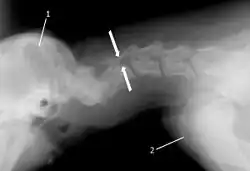

The disease tends to be gradually progressive. Symptoms such as weakness, ataxia, and dragging of the toes start in the rear legs. Dogs often have a crouching stance with a downward flexed neck. The disease progresses to the front legs, but the symptoms are less severe. Neck pain is sometimes seen. Symptoms are usually gradual in onset, but may progress rapidly following trauma.[6] X-rays may show misaligned vertebrae and narrow disk spaces, but it is not as effective as a myelogram, which reveals stenosis of the vertebral canal. Magnetic resonance imaging has been shown to be more effective at showing the location, nature, and severity of spinal cord compression than a myelogram.[7] Treatment is either medical to control the symptoms, usually with corticosteroids and cage rest, or surgical to correct the spinal cord compression. The prognosis is guarded in either case. Surgery may fully correct the problem, but it is technically difficult and relapses may occur. Types of surgery include ventral decompression of the spinal cord (ventral slot technique), dorsal decompression, and vertebral stabilization.[8] One study showed no significant advantage to any of the common spinal cord decompression procedures.[9] Another study showed that electroacupuncture may be a successful treatment for Wobbler disease.[10] A new surgical treatment using a proprietary medical device has been developed for dogs with disc-associated wobbler disease. It implants an artificial disc (cervical arthroplasty) in place of the affected disc space.[11]